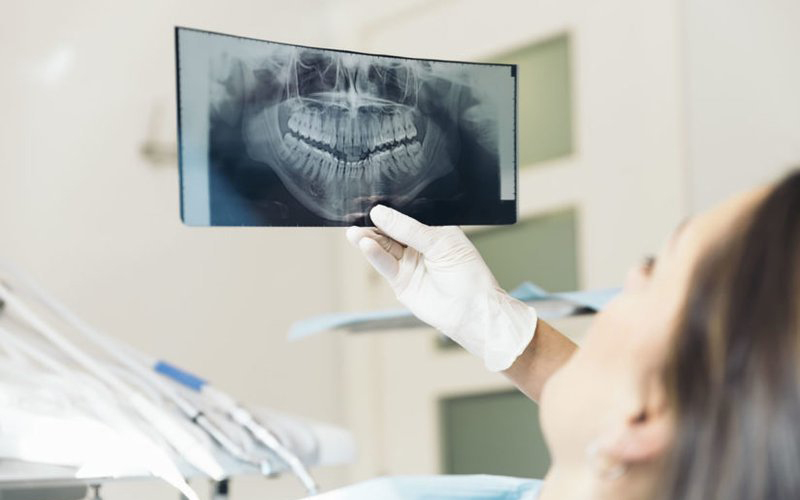

Chụp X-quang là phương pháp sử dụng tia X, một loại bức xạ điện từ, để tạo ra hình ảnh các cấu trúc bên trong cơ thể. Khi tia X đi qua cơ thể, chúng bị hấp thụ bởi các mô khác nhau ở mức độ khác nhau. Các mô đặc như xương hấp thụ nhiều tia X, còn mô mềm như cơ hay phổi hấp thụ ít hơn. Điều này tạo ra sự tương phản giúp hình ảnh thu được rõ ràng hơn.

Quá trình chụp X-quang diễn ra nhanh chóng, chỉ mất vài phút, hình ảnh được ghi lại trên phim hoặc lưu trữ kỹ thuật số để bác sĩ phân tích. Tính chính xác của phương pháp này giúp phát hiện các bất thường từ những thay đổi nhỏ nhất trong cơ thể, đặc biệt là trong các trường hợp bệnh lý tiềm ẩn.